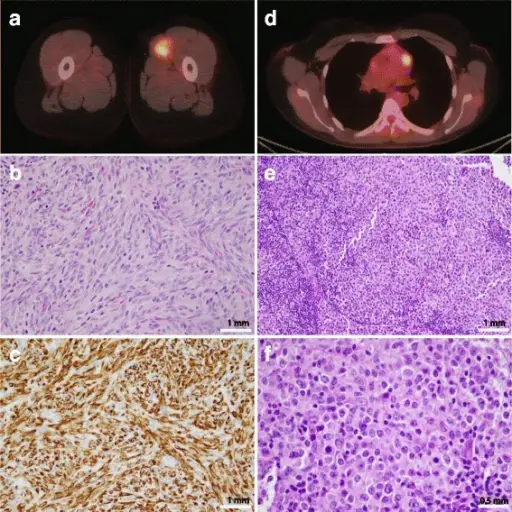

Rhabdomyosarcoma

Rhabdomyosarcomas are malignant tumors composed mainly of skeletal muscle.

Rhabdomyomas typically effect skeletal muscle, or occasionally hollow organs like the bladder or uterus.

Diagnosis is made by histology showing malignant skeletal muscle with rhabdomyoblasts, which are the characteristic cells of rhabdomyosarcoma.

Pathology stains for rhabdomyosarcoma will be desmin stain positive.

Rhabdomyosarcomas often involve the head and neck in the majority of patients, but the vagina is the classic site in young girls.